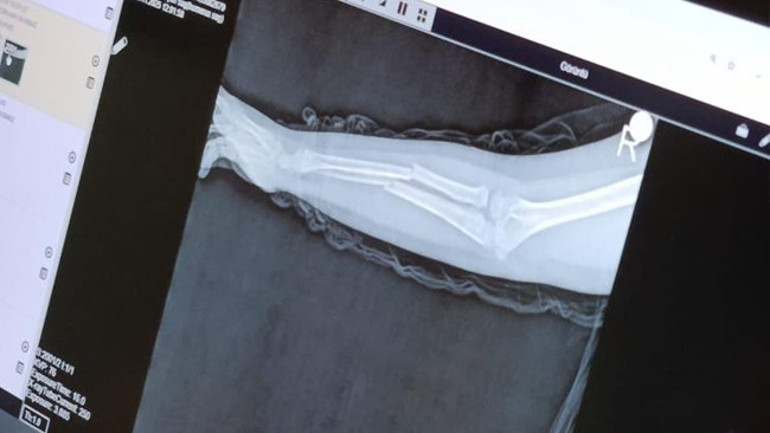

Olay, geçtiğimiz ay Büyükçekmece Tepecik'te bulunan bir ilkokulda meydana geldi. İddiaya göre 8 yaşındaki Y.K.Ş. okulda bir süredir kendisini rahatsız eden 9 yaşındaki çocuk tarafından darp edilerek kolu ikiye katlandı. Y.K.Ş.'nin 2'ye katlanan kolu 2 ayrı yerinden kırıldı. Öğretmenler Y.K.Ş.'nin ailesini arayarak, ‘oğlunuz arkadaşıyla kavga etti duvara çarptı' denildi. Oğlunu okuldan alıp hastaneye götüren anne Songül Gökdemir, oğlunun kolunun 2 ayrı yerinden kırıldığını öğrenip ameliyata alınacağını duyduğunda büyük şok yaşadı.

Konuyla ilgili anne Gökdemir savcılığa giderek şikayetçi oldu. Savcılıktan ise 'söz konusu Suça Sürüklenen Çocuğun yaşının 12'den küçük olduğu gerekçesi ile kovuşturmaya yer yoktur' kararı çıktı. Anne Gökdemir karara itiraz ederken mağdur Y.K.Ş. ise haftalardır okula gidemiyor. Eğitimi aksayan çocuğun 2 hafta sonra ise platinlerinin çıkarılması için yeniden ameliyata gireceği öğrenildi.

Yaşanan olayı anlatan Songül Gökdemir, " Arkadaşlarından darbe aldığını biliyordum. Ayrıca Eylül ayından bu yana bir arkadaşının onun kolunu kırmaya çalıştığını söyledi. Ben de 'arkadaşını öğretmene söyle' dedim. Bundan kaçıyordu. O gün de rehber öğretmenine bu arkadaşını şikayet ettiler. Ben işe gittim 1 saat sonra öğretmeni aradı. Oğlunuz arkadaşıyla birbirini itekledi kolunu duvara çarptı gelir misiniz ?' dedi. Kendi imkanımla hastaneye götürdüm. Okula gittiğimde de oğlum derste oturuyordu. Öğretmen ders işliyordu ambulans çağırılmamış. Hastanede kolunda 2 tane kırık olduğunu acilen de ameliyata girmesi gerektiğini öğrendim. 3 gün sonra ameliyata alındı. Kolundaki platinlerden dolayı her gün pansumanı var. 2 hafta sonra tekrar ameliyatı var" dedi.